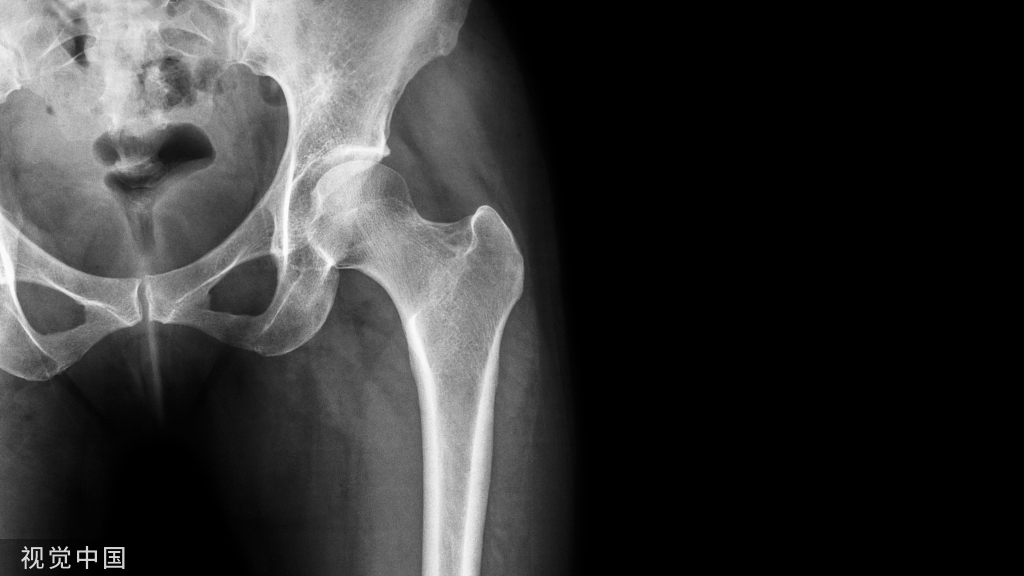

锚钉可用于:肩关节、肘关节 、手和腕关节、膝关节 、足和踝关节、颌面部、髋关节、骨盆